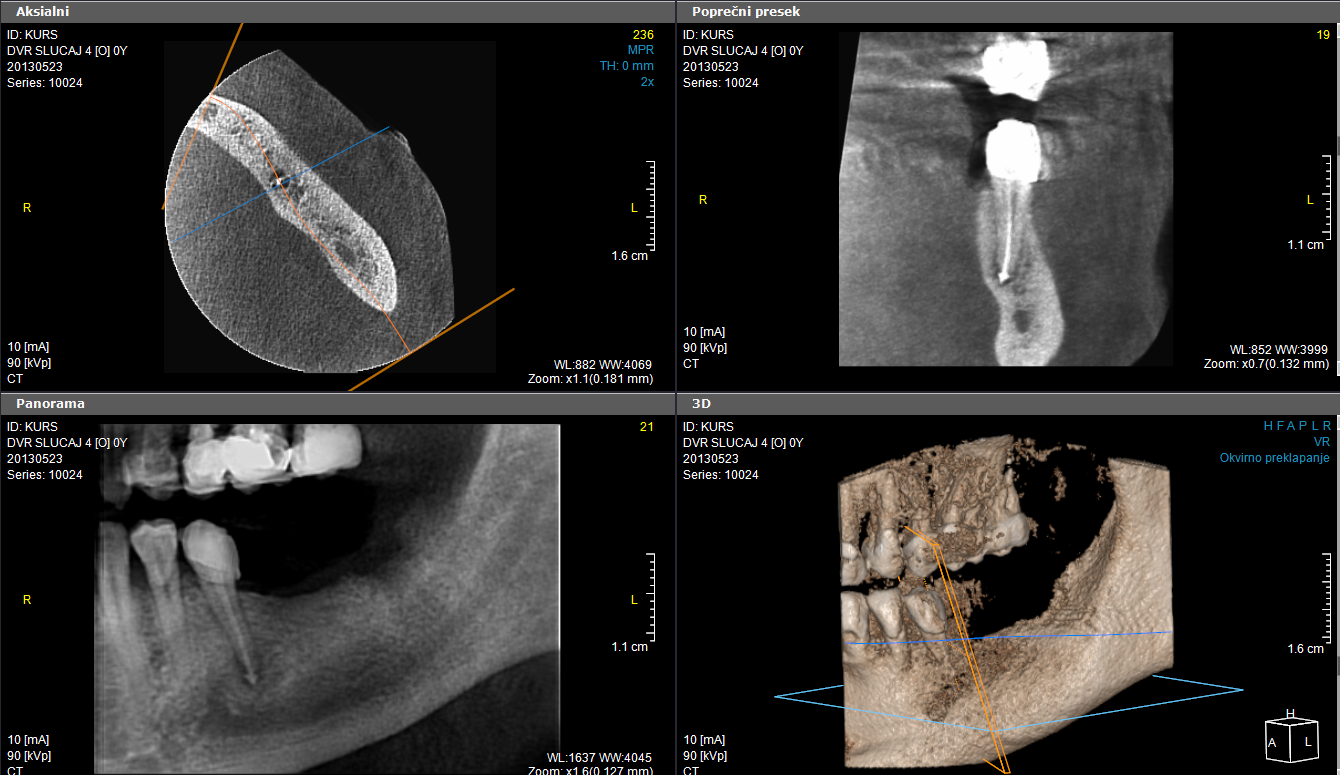

У оквиру софтвера се добија радиолошки и дентални модул са опцијом планирања имплантата и базом свих тржишно доступних имплантата.

6x4цм, стандардна резолуција

6х4цм, ENDO резолуција

6х8см, висока резолуција

6х8цм, протокол ниске дозе

11x8цм, стандардна резолуција